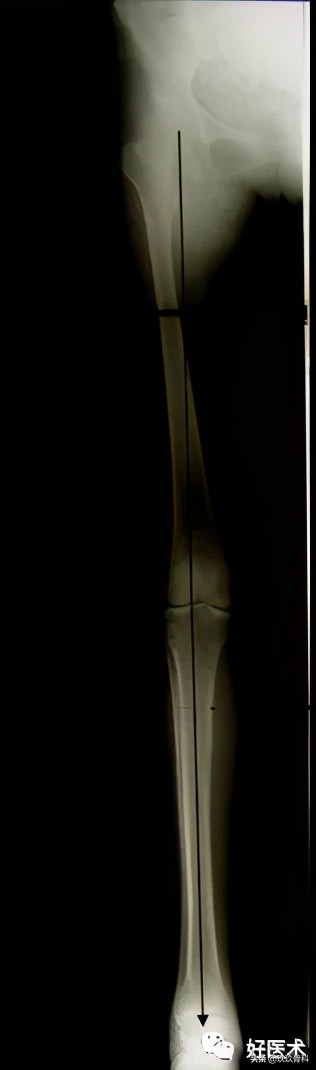

9.术中控制力线的技术

- 冠状面--钢缆技术(cable technique)

- 矢状面--侧位影像增强仪

2)股骨旋转的X线征象

- 小粗隆形状

- 皮质台阶征:通过近端和远端主要骨块的皮质厚度判断力线→横行、短斜形骨折

- 直径差异征:骨直径是卵圆形节段,旋转畸形,远、近端骨折的横径在不同直径部位突出